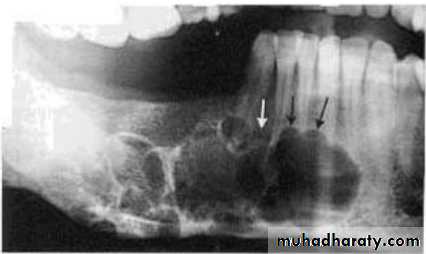

Cystic ameloblastoma displaced IDC (odontogenic origin)

Epicenter coronal to tooth(odontogenic epithelium )